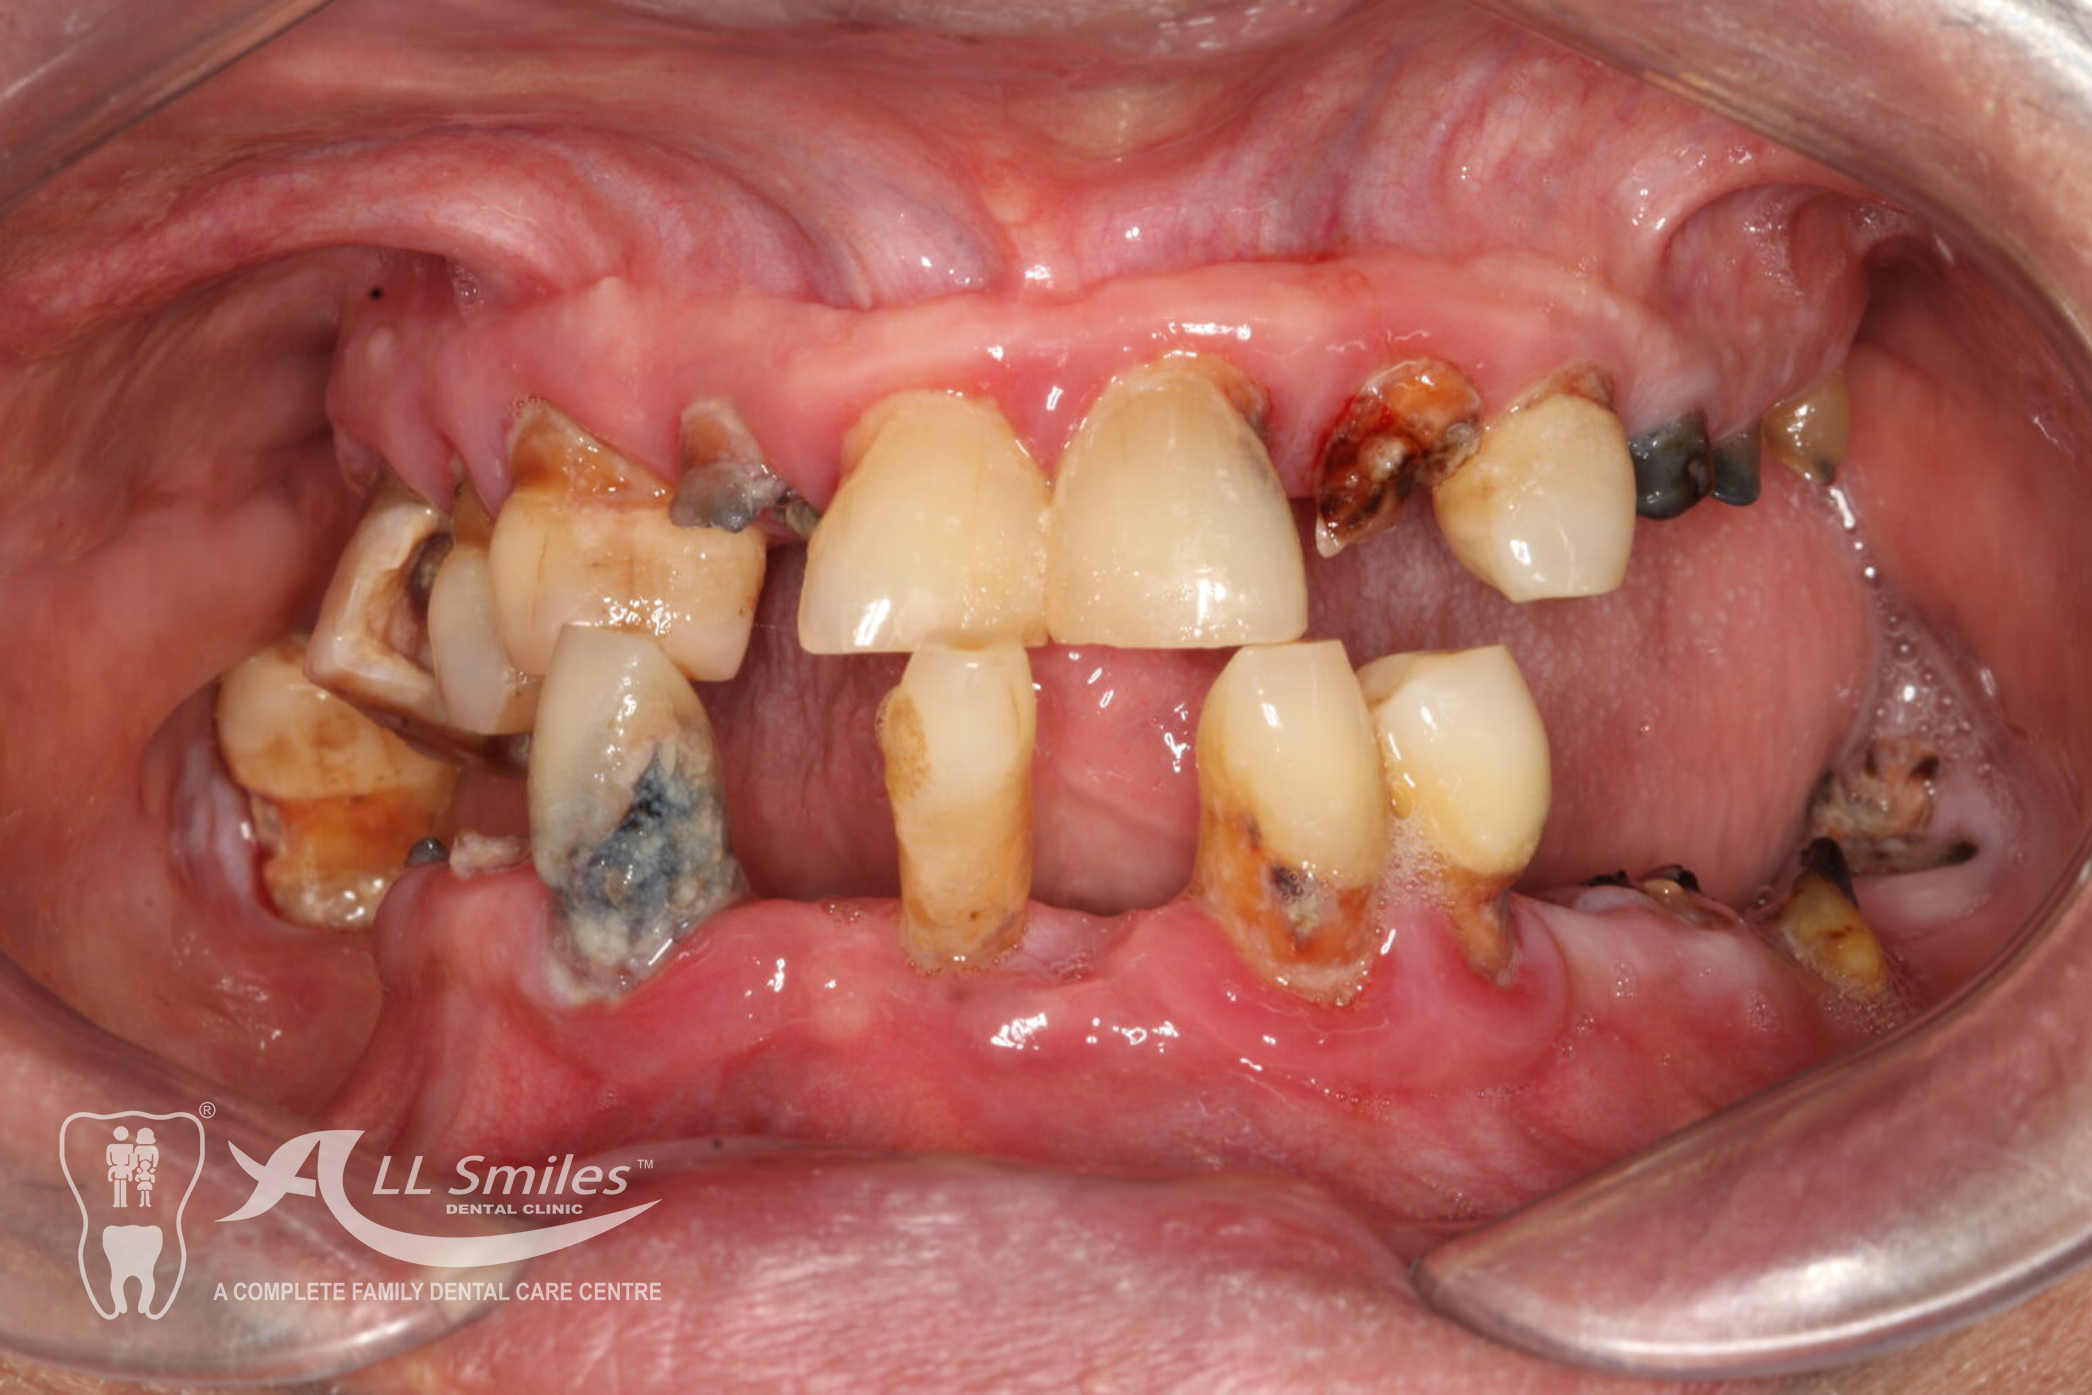

Implants For Multiple Missing or Broken Teeth Regardless of whether one or more teeth are missing in a row: Every tooth is individually replaced and the situation is restored to its original condition. If three or more teeth in a row are missing, you can decide to have an implant- borne bridge. In this solution the new crowns are linked together and depending on the size of the gap are placed on a stable and secure base of two or more implants .

After precise planning the new tooth roots are generally placed in the jaw in one single treatment session. A temporary denture closes the gaps during the healing phase. After healing the final crowns or the bridge are permanently fixed to the implants. Life With Bite! Dental Implants For The Edentulous Jaw.

Dental Implants Gallery